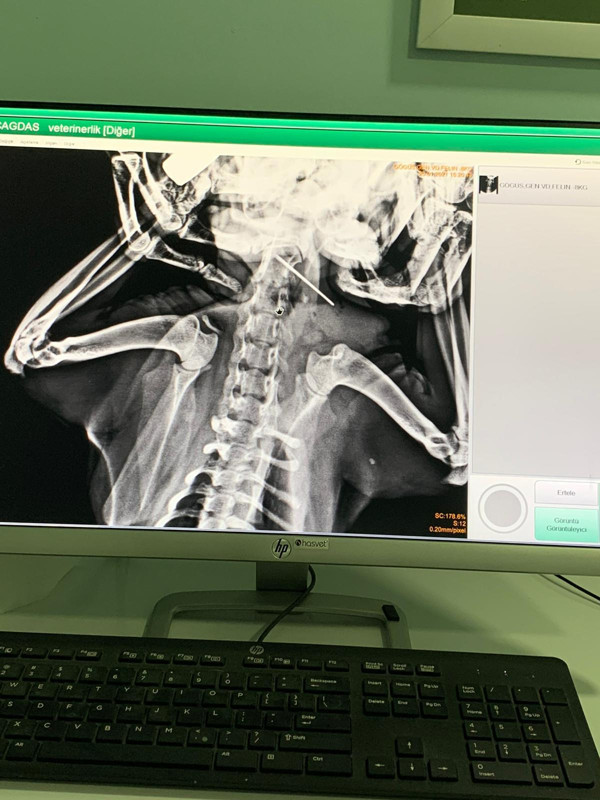

Ortakçı, röntgende kedinin yemek borusunun ortasında 6 santim uzunluğunda ve ucunda ip olan dikiş iğnesini tespit etti. Veteriner hekim Ortakçı, Anestezi uygulayarak uyuttuğu kediyi, yarım saatlik ameliyatın ardından dikiş iğnesini çıkardı. Başarılı operasyonun ardından Maviş, sahibi Serkan Yılmaz’a teslim edildi.

Kedisinin hareketlerinin yavaşlamaması ve yemek yememesinden şüphelenerek, veteriner kliğine götürdüğü belirten Serkan Yılmaz, "Veteriner hekim Olcay Ortakçı, yapılan muayede kedinin ağzında kireçlenmeden dolayı enfeksiyon oluştuğunu söyledi. Sonra emin olmak için kedinin röntgeni çekildi. Röntgende boğazında dikiş iğnesi olduğunu tespit etti. Yarım saatlik operasyonunun ardından iğne bulunduğu yerden çıkartıldı. Şu anda ilaçlarını kullanıyor. Sağlığı gayet yerinde eski haline döndü” dedi.